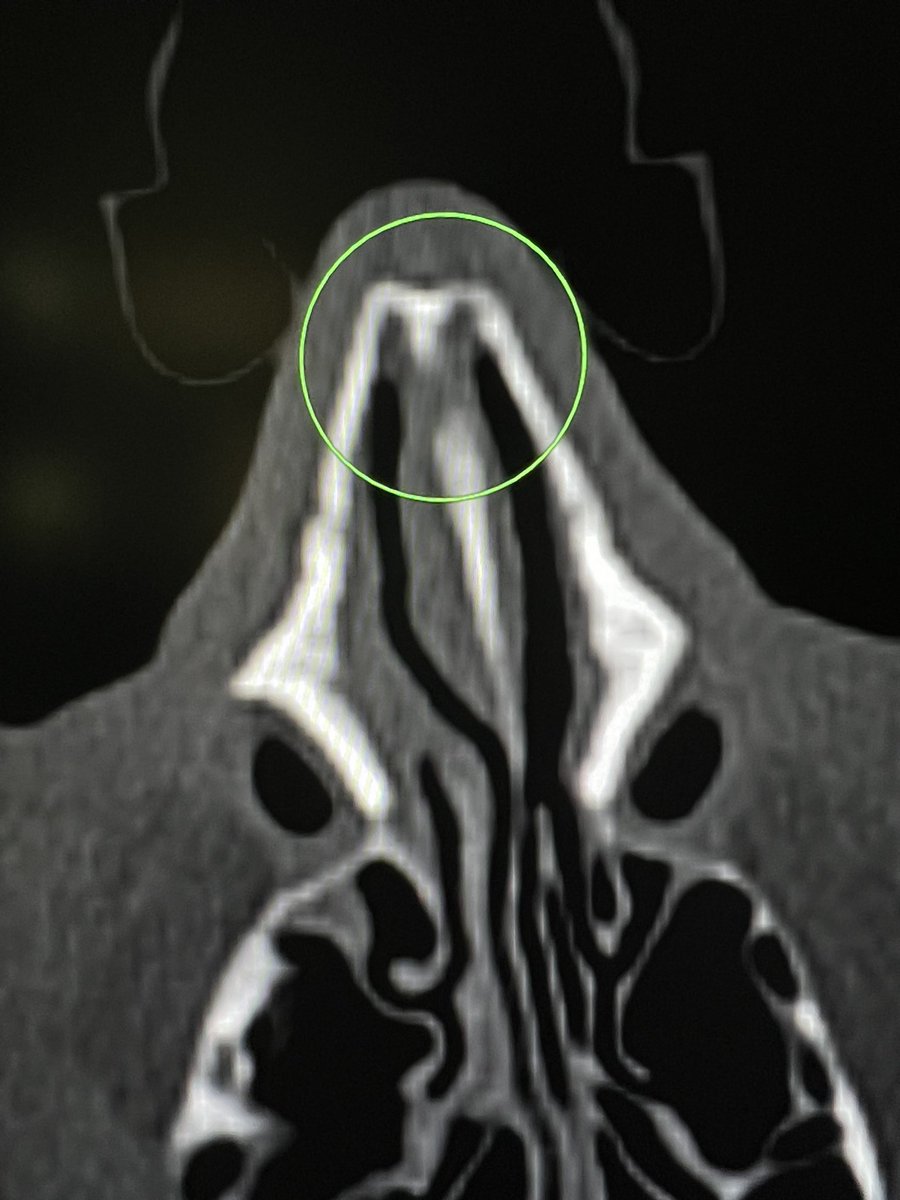

Sameer Raniga

Absence soft tissue swelling or preservation of air in this triangular portion of the nasal cavity (deep/medial to the nasal bone and lateral to the nasal septum)- has almost 100% negative predictive value for a nasal bone fracture (excludes nasal fracture). I don’t look at the bone window if this region is clear and contains air. —on-call wisdom

Sameer Raniga tweet mediaSameer Raniga tweet media